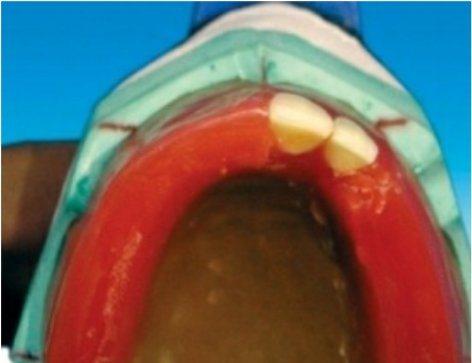

Placement of the maxillary central incisor in relation to all three planes.

🔻The long axis of the central incisor (the blue line) is positioned parallel to the

vertical axis (the red line) when viewed from the front

🔻The incisal edge of the maxillary central incisor is positioned in line with the

anterior occlusal plane . The central pin of the articulator will point the mesioincisal line edge of the central incisor.

🔻The central pin of the articulator will

point the mesioincisal line edge of the central incisor.

When viewed from:

Front: Long axis parallel towards the vertical axis.

Side: Slopes labially about 15 degrees.

Occlusal plane: Incisal edge is in contact with occlusal plane

🔻The long axis of the lateral incisor (green line) is placed slightly inclined to

the vertical axis (red line).

🔻The incisal edge of the maxillary lateral incisor is placed slightly short of the

occlusal plane (marked as yellow line).

🔻The incisal edge of the maxillary lateral incisor should follow the outline of

the occlusal rim when viewed occlusally

When viewed from:

Front: Long axis slopes towards midline at incisal edge.

Side: Slopes labially about 20 degrees.

Occlusal plane: Incisal edge is 1 mm short of occlusal plane